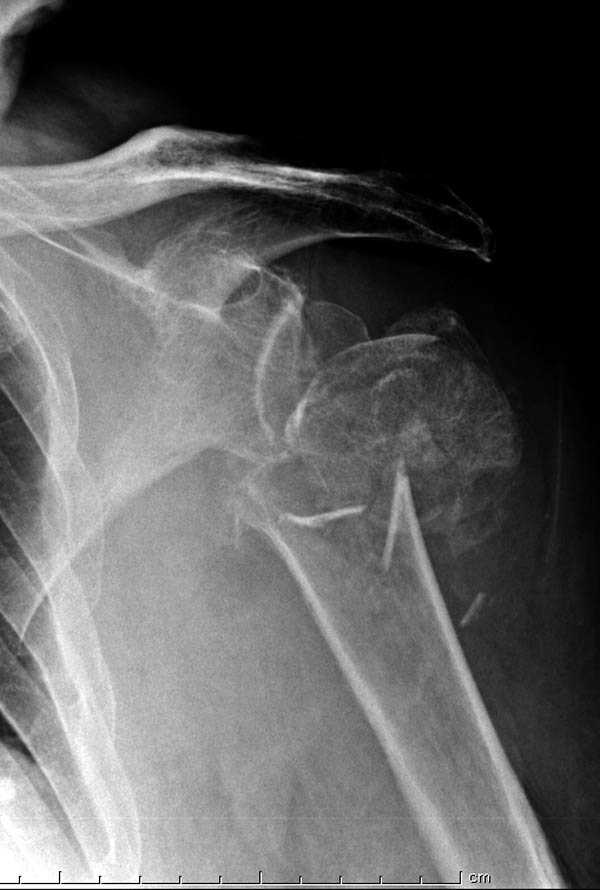

Пациентка Б.1953 г.р., врач-терапевт. Травма 27.11.08г. Падение с высоты роста. Выявлен закрытый не осложненный оскольчатый перелом хирургической шейки левого плеча со смещением. 02.12.08г. оперирована. Выполнена открытая репозиция и остеосинтез пластиной LCP Деост с дополнительной фиксацией отдельно лежащего фрагмента винтом. Послеоперационный период протекал без особенностей, заживление раны первичным натяжением. Швы сняты через 10 дней. Иммобилизация левой верхней конечности клиновидной подушкой 4 недели. По окончании срока – рентген-контроль и умеренная разработка плечевого сустава. В течении месяца функция левого плечевого сустава восстановилась удовлетворительно: поднятие руки до 110 гр., отведение - 90 гр. и до 110 гр. отведение с лопаткой. Отведение руки назад – 20 гр. Наружная и внутренняя ротация – 20 гр. Пациентка по настоянию самостоятельно вышла на работу. 27.03.09 при контрольном осмотре жалоб не предъявляет, болевой синдром в левом плечевом суставе отсутствует. Отведение плеча активно до 90 гр, пассивно с лопаткой до 110 гр., поднятие – 110 гр, отведение назад 20 гр, наружная и внутренняя ротация по 20 гр. На контрольных рентгенограммах отмечается смещение металлоконструкции, ротация головки плеча с приведением дистального отломка на 13 гр. и смещением к зади на 30 гр. Рентгенограммы прилагаются. Ваш взгляд на дальнейшую тактику лечения пациентки?

Уважаемый Евгений, похоже, что первый и второй Р-снимки выполнены несколько в разных положениях(ротация) плечевой кости, в связи с этим создается впечатление смещения пластины. Остеосинтез выполнен при угловом смещении отломков.Таковым и остался. Данная ситуация была бы очевидна гораздо раньше, если бы при контрольной Р-графии были выполнены снимки в 2-х проекциях.(Не в обиду, сам иногда выполняю только один).